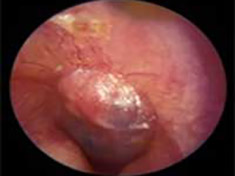

Acute Infection with bulging of the tympanic membrane due to pressure from purulence (pus) behind it. The last picture reveals an ear tube that has gotten prematurely blocked and the ear is once again infected.